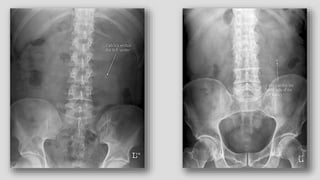

Scoliosis of spine and compression of the

urinary bladder

PSOAS ABSCESS